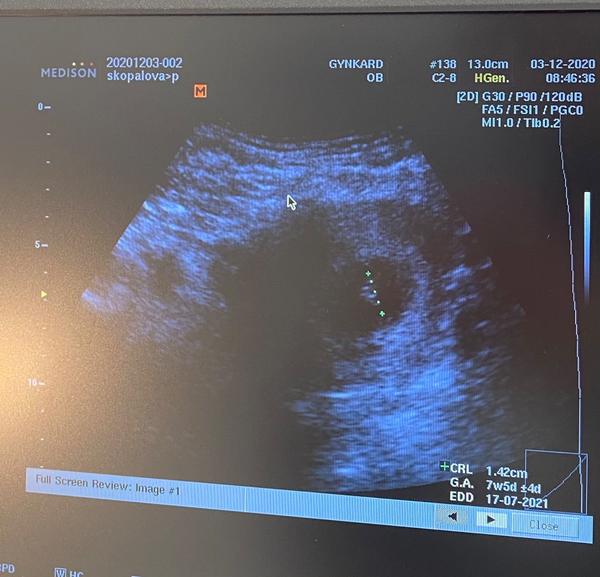

10.3 jsem měla pozitivní těhotenský test. Měla bych tedy být 6+4. Dnes jsem šla na první kontrolu, kde doktor viděl pouze prázdný plodový vak. Řekl že plod se může ještě vyvinout a mám přijít na další kontrolu za tři týdny.

Fotku našeho prázdného vaku mám dodnes schovanou. Letos už bude mít 6 let. Naděje je vždycky, ať to dobře dopadne!